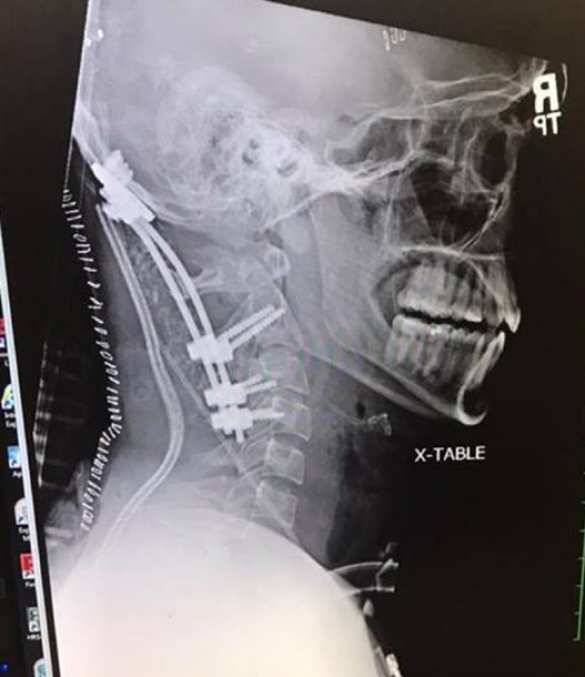

Врачи диагностировали у него атланто-затылочную дислокацию — то самое «внутреннее обезглавливание». Практически во всех известных случаях она оказывалась смертельной.

Хирурги провели сложнейшую операцию, закрепив в шее мужчины металлические штифты, которая оказалась успешной.